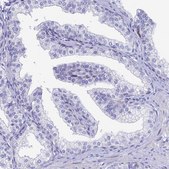

Application:

IHC

All Prestige Antibodies Powered by Atlas Antibodies are developed and validated by the Human Protein Atlas (HPA) project and as a result, are supported by the most extensive characterization in the industry.

The Human Protein Atlas project can be subdivided into three efforts: Human Tissue Atlas, Cancer Atlas, and Human Cell Atlas. The antibodies that have been generated in support of the Tissue and Cancer Atlas projects have been tested by immunohistochemistry against hundreds of normal and disease tissues and through the recent efforts of the Human Cell Atlas project, many have been characterized by immunofluorescence to map the human proteome not only at the tissue level but now at the subcellular level. These images and the collection of this vast data set can be viewed on the Human Protein Atlas (HPA) site by clicking on the Image Gallery link. We also provide Prestige Antibodies® protocols and other useful information.

• IHC tissue array of 44 normal human tissues and 20 of the most common cancer type tissues.